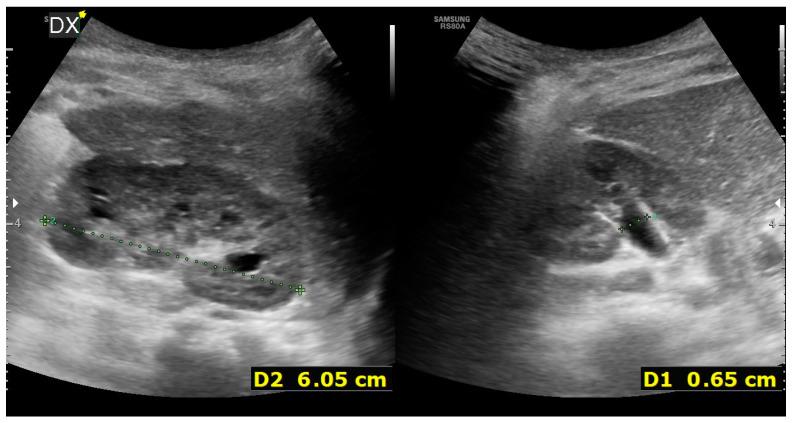

A two-month-old boy, without antenatal and postnatal signs of urinary tract anomalies, was hospitalized presenting right hydronephrosis, perirenal fluid effusion, and ascites. An acute pelvic rupture was suspected, and a retrograde pyelogram was performed, showing a primary obstructive megaureter (POM) associated with a corkscrew pyeloureteral junction. The impossibility to place a double J catheter through the pyeloureteral junction led us to achieve percutaneous nephrostomy and an abdominal drain placement. Three months later, the patient underwent a combined high-pressure balloon ureterovesical junction dilation and retroperitoneoscopic Anderson Hynes one-trocar-assisted pyeloplasty (OTAP). The literature search identified 110 children experiencing double urinary tract obstruction. All authors agreed on the difficulty to diagnose both obstructions preoperatively, but there is still no consensus on which obstruction should be relieved earlier, because the alteration in urinary vascularity during a double surgery could damage the ureter.

一名两个月大的男婴,产前和产后均无尿路异常体征,因右侧肾积水、肾周积液和腹水入院。怀疑有急性盆腔破裂,遂行逆行肾盂造影,显示原发性梗阻性巨输尿管(POM)合并螺旋状肾盂输尿管连接部。无法通过肾盂输尿管连接部置入双J导管,于是我们进行了经皮肾造瘘术和腹腔引流管置入术。三个月后,患者接受了高压球囊输尿管膀胱连接部扩张术和后腹腔镜Anderson Hynes单孔辅助肾盂成形术(OTAP)。文献检索发现110例儿童存在双重尿路梗阻。所有作者都认同术前诊断两种梗阻存在困难,但对于应先解除哪种梗阻仍未达成共识,因为二次手术期间尿路血供的改变可能会损伤输尿管。